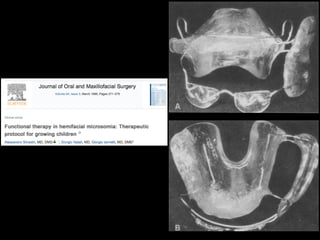

Hybrid functional appliance have to be used to correct the asymmetry.

Hybrid of bionator in the right side and Frankell II in the left side.